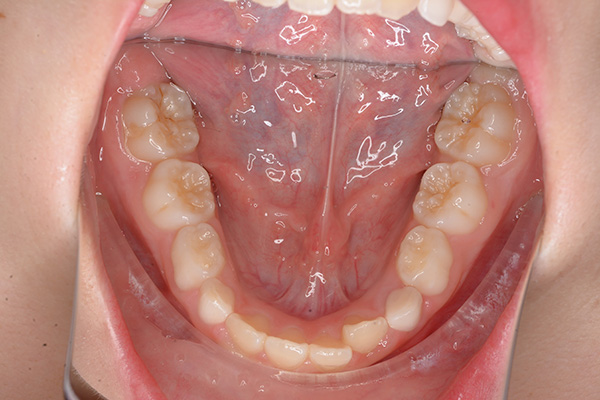

動的治療開始前(9歳7ヵ月)

動的治療開始前

(9歳7ヵ月)

口腔内所見 over jet -2.5mm、over bite 2.0mm、大臼歯関係はⅠ級 。Hellmanのdental ageはⅡCであり前歯部は反対咬合を呈していた。

パノラマ所見 上顎アーチレングスディスクレパンシー(-)であるが、その他の異常所見は認められなかった。